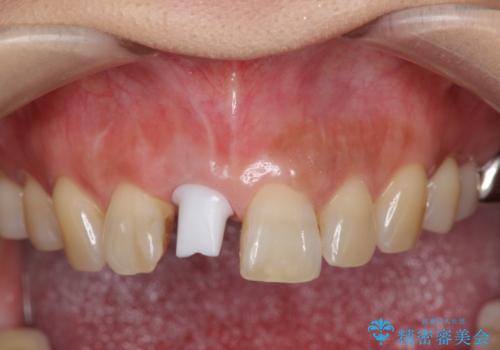

骨造成を伴う前歯のインプラント治療

- 前歯を外傷により失い、審美性の改善を求めて来院されました。

横の歯を削る必要のあるブリッジ治療、着脱の必要な入れ歯に強い抵抗があったためインプラント治療を計画します。

審美的・機能的に良好な位置に埋入するには、骨量が十分ではなかったため骨の造成を併用したインプラント埋入外科手術を行います。

前歯のインプラントを審美的に仕上げるには、インプラント周囲に十分な骨の量と厚みのある歯肉、そして埋入位置の精密な位置付けが重要です。